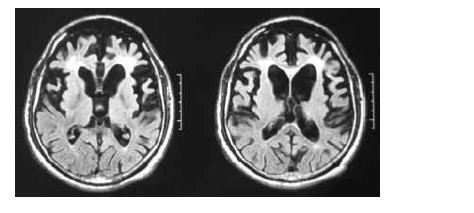

Uma mulher de 55 anos de idade, sem comorbidades, há três anos começou a apresentar distúrbio do comportamento, comprometimento do senso moral, da autocrítica, do poder de abstração e da memória. No exame, ela pouco colaborava com o examinador, possuía uma rigidez axial e apendicular, além de sutil tremor em repouso. O exame de imagem (RNM) a seguir foi realizado para auxiliar o diagnóstico.